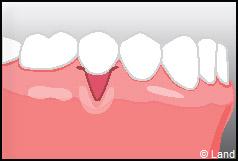

Outre la maladie parodontale, nous pouvons rencontrer des défauts de la gencive qui n’ont pas une origine infectieuse. Les plus fréquents de ces défauts sont les récessions gingivales, qui se traduisent par la migration de la gencive en direction de la racine (la racine est alors à nu).

Les conséquences de cette mise à nu de la racine dentaire sont multiples, le patient peut présenter une hypersensibilité dentaire et l’aspect de ces récessions peut être inesthétique. Dans ce cas, la chirurgie muco-gingivale est recommandée et elle peut se faire de différentes façons.

Dans ce cas le lambeau est déplacé latéralement pour combler la récession.